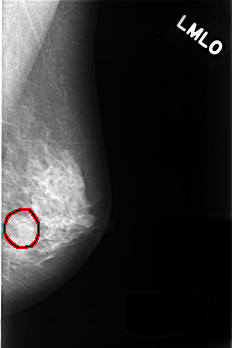

FILE: C_0426_1.LEFT_MLO.OVERLAY

TOTAL_ABNORMALITIES 1

ABNORMALITY 1

LESION_TYPE MASS SHAPE OVAL MARGINS CIRCUMSCRIBED

ASSESSMENT 3

SUBTLETY 4

PATHOLOGY BENIGN_WITHOUT_CALLBACK

TOTAL_OUTLINES 1

BOUNDARY

LEFT_MLO LINES 4512 PIXELS_PER_LINE 3008 BITS_PER_PIXEL 12 RESOLUTION 50 OVERLAY